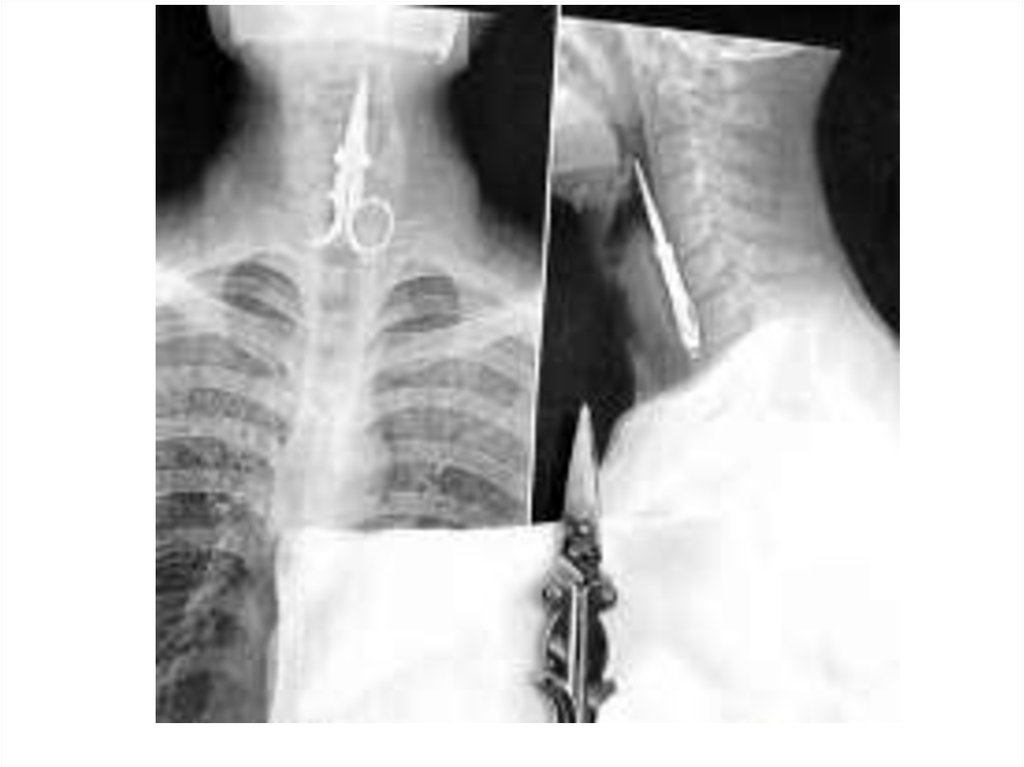

• Среди рентгенологических признаков

повреждений пищевода следует различать

косвенные признаки и прямые.

• Косвенные признаки можно определить при

полипозиционной рентгеноскопии шеи и грудной

клетки, выявленные изменения фиксируются затем

на рентгенограммах. Наиболее распространенным

признаком повреждения пищевода является

наличие эмфиземы околопищеводной

клетчатки шеи и средостения, межфасциальных

пространств шеи, подкожной клетчатки.

Возникновение пневмоторакса,

гидроторакса или гидропневмоторакса также

является косвенными признаками разрыва

пищевода.